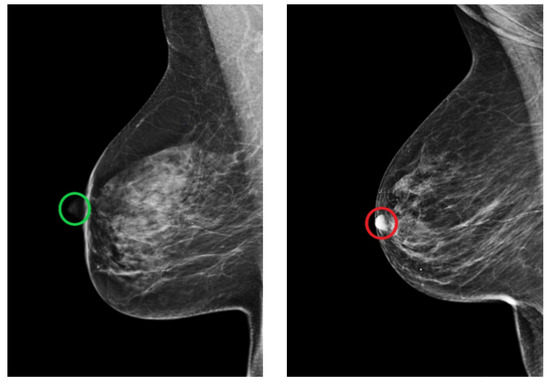

The MLO view is also assessed by looking for the position of the nipple. In a well-positioned mammogram, the nipple should be in profile. Once it is projected onto the parenchyma, it may overlap a lesion and result in undetected malignancy. Figure 22 shows an example of adequately and inadequately positioned MLO views regarding the nipple position.

Figure 22. Example of adequately (green circle) and inadequately (red circle) positioned MLO views regarding the position of the nipple. (Left): in profile. (Right): projected onto the parenchyma.